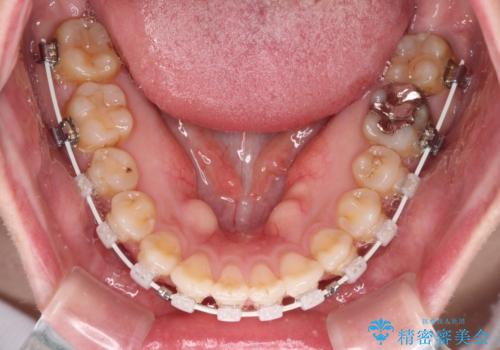

舌突出癖による開咬 舌のトレーニングを行いながら咬み合わせを改善

前歯のデコボコはもちろん気になるところですが、舌の突出癖により上下前歯が非接触となっている状態でした。

上下前歯が非接触である開咬は、インビザラインによる治療がお勧めではありますが、しっかりと使う自信がないとのことで、ワイヤー装置にて治療を行うこととしました。

デコボコはあっという間に改善されましたが、開咬の改善に時間がかかりました。

舌の突出癖改善のトレーニングをしっかりと行っていただき、上下前歯が接触する咬み合わせを達成することができました。